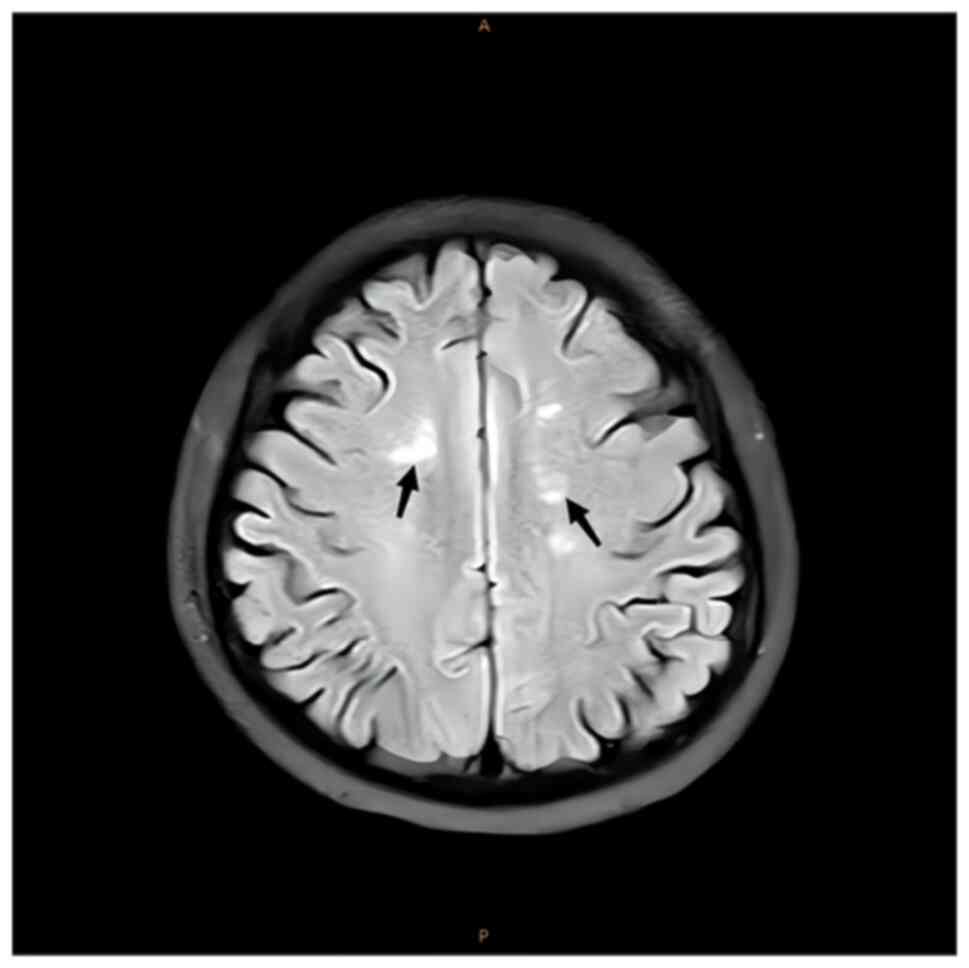

Magnetic resonance imaging (MRI) of the cervical and

thoracic spinal cord indicated an abnormal T2-weighted

intramedullary signal with a high signal (Figs. 1 and 2). Axial images indicated that the

lesions mainly occupied the posterior portion of the spinal cord in

a ‘figure-eight sign’ (Figs. 3 and

4). MRI of the brain demonstrated

spot-like and short-stripe abnormal signals that were distributed

symmetrically in the centrum semiovale, with equal or a slightly

low signal intensity on T1W1 and a slightly high signal intensity

on T2W1 (Fig. 5) and

hyperintensity on fluid-attenuated inversion recovery (FLAIR;

Fig. 6). Diffusion-weighted

imaging revealed low signal intensity (Fig. 7) and the long axis of the lesion

was perpendicular to the lateral ventricles. The patient was

finally diagnosed with SCD.

weakness, sensory ataxia and paraesthesia (11). In the present study, the patient's

lesions were mainly in the bilateral centrum semiovale as there was

a high signal in this region on T2 MRI and FLAIR. In the present

study, the lesions were symmetrical and perpendicular to the long

axis of the bilateral lateral ventricles, which is a characteristic

manifestation of SCD. These lesions are either directly or

indirectly related to the vitamin B12 deficiency observed in the

patient.